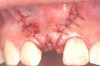

Fig 7. Vertical releasing incisions sutured to attain primary closure, buccal view.

Figure 7